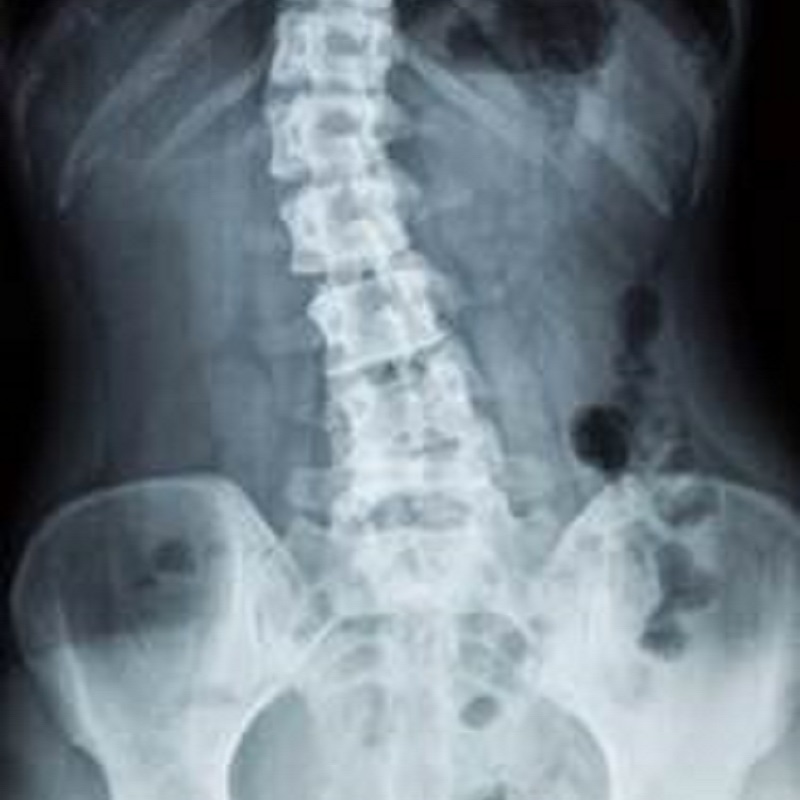

腰椎由五塊椎骨組成,腰椎沿矢狀面形成"前突後凹"的正常生理弧度。腰部靠韌帶和肌肉維持挺直的姿勢,韌帶包括前、後縱韌帶,黃韌帶,棘間和棘上韌帶;不同層次的肌肉維持腰部姿勢,其中的深層肌肉,包括半棘肌(Semispinalus)、多裂肌(Multifidus)及外圍的環腹肌組成的腰部核心肌群,能幫助腰在活動時保掠動態穩定。

腰椎可產生痛症的組織可括椎間盤的纖維環及髓核、椎間關節、韌帶、肌肉、神經線及關節囊。約80%腰痛患者的診斷為軀體疼痛( Somatic Pain);另外的20%為內臟引起的腰痛。

- 脊柱側彎

脊柱側彎:

冠狀面或額狀面脊柱非直線型狀,呈C字型或S字型。可再分為功能性和結構性脊柱側彎。